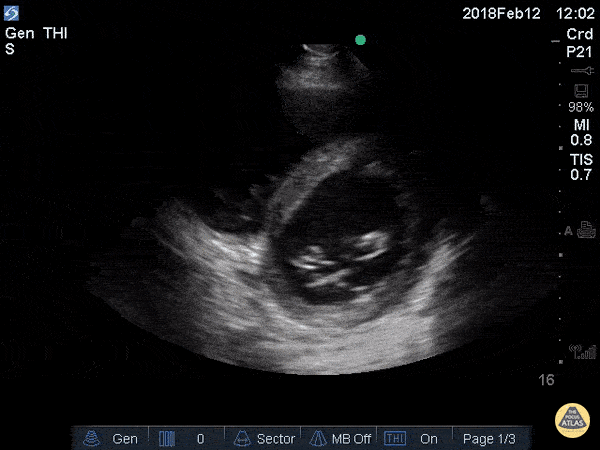

Cardiac Ultrasound for the case found here:

(U/S source: http://www.thepocusatlas.com/echo/2hj4yjl0bcpxxokzzzoyip9mnz1ck5)